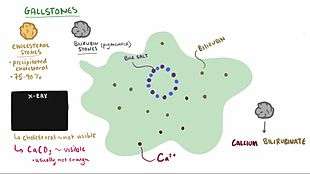

Cholesterol stones

Cholesterol stones vary from light yellow to dark green or brown or chalk white and are oval, usually solitary, between 2 and 3 cm long, each often having a tiny, dark, central spot. To be classified as such, they must be at least 80% cholesterol by weight (or 70%, according to the Japanese- classification system).[30] Between 35% and 90% of stones are cholesterol stones.[3]

Bilirubin stones

Bilirubin ("pigment", "black pigment") stones are small, dark (often appearing black), and usually numerous. They are composed primarily of bilirubin (insoluble bilirubin pigment polymer) and calcium (calcium phosphate) salts that are found in bile. They contain less than 20% of cholesterol (or 30%, according to the Japanese-classification system).[30] Between 2% and 30% of stones are bilirubin stones.[3]

Mixed stones

Mixed ("Brown Pigment") stones typically contain 20–80% cholesterol (or 30–70%, according to the Japanese- classification system).[30] Other common constituents are calcium carbonate, palmitate phosphate, bilirubin and other bile pigments (calcium bilirubinate, calcium palmitate and calcium stearate). Because of their calcium content, they are often radiographically visible. They typically arise secondary to infection of the biliary tract which results in the release of β-glucuronidase (by injured hepatocytes and bacteria) which hydrolyzes bilirubin glucuronides and increases the amount of unconjugated bilirubin in bile. Between 4% and 20% of stones are mixed.[3]